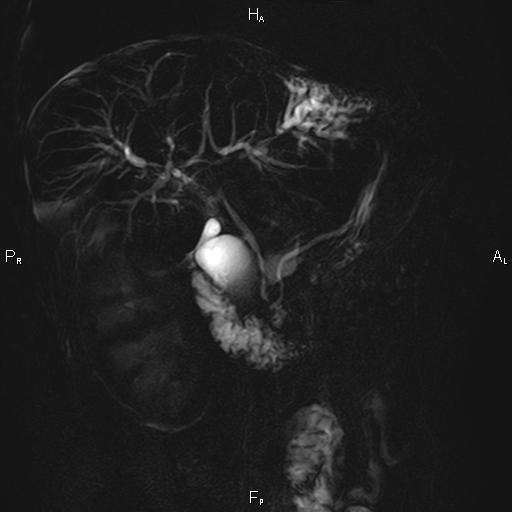

Ανώδυνος ίκτερος και παθολογικά ηπατικά ένζυμα. Ιστορικό πιθανής σκληρυντικής χολαγγειίτιδας

Μαγνητική τομογραφία.

Οι αρχικές εξετάσεις εκλογής, όσον αφορά τον απεικονιστικό κυρίως έλεγχο, σε ασθενή προσερχόμενο στο Νοσοκομείο με αποφρακτικό ίκτερο, είναι το υπερηχογράφημα και η αξονική τομογραφία. Οι εξετάσεις αυτές έχουν αποδειχθεί ικανές να προσδώσουν έμμεσα και άμεσα στοιχεία για τη διάγνωση του χολαγγειοκαρκινώματος, όμως κυρίαρχη εξέταση για την διάγνωση του χολαγγειοκαρκινώματος είναι η μαγνητική τομογραφία (MRI, MRCP, MRA).